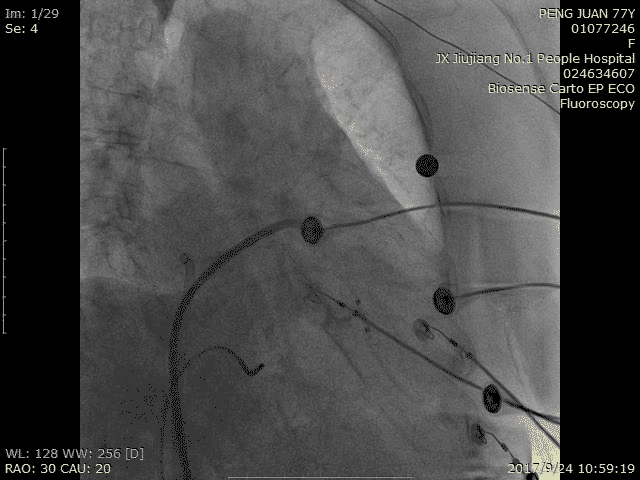

射频消融:

术中造影:

RAO 30 CRA 20:

RAO 30 CAU 20: